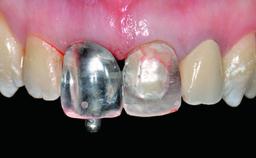

Replacement of a Perforated Upper Left Central Incisor: Early Placement of an RC Bone Level Implant

A 28-year-old patient presented at her general dentist’s office and complained about the appearance of her tooth 21. The patient had a history of trauma to this tooth. Endodontic treatment had been performed in the past and a crown placed on the tooth. A procedure to replace the old crown was performed by her dentist; however, a perforation on the middle third of the root occurred, and extraction of tooth 21 was suggested. Upon clinical and radiographic examination of the patient, who had been referred to us, replacement of tooth 21 by a dental implant appeared to be indicated.

Abutment Type Customized

Prosthesis Type FDP